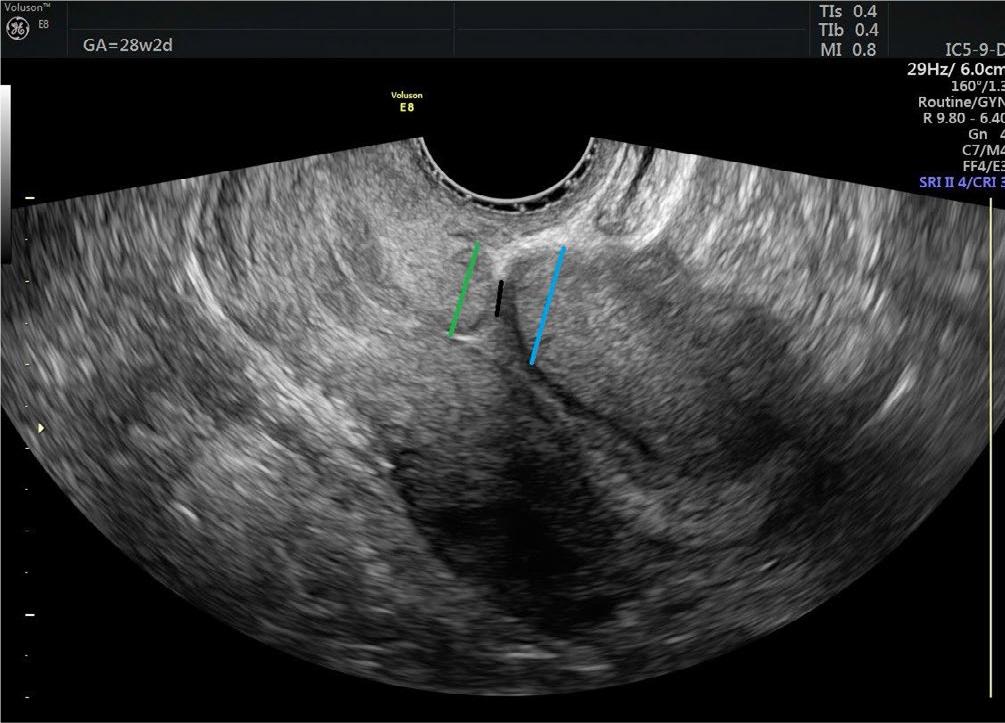

Fig. 2.